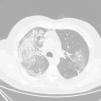

On the first day of admission, the patient presented with isolated bloody sputum, which, along with anaemia and parenchymal condensation, led to a suspected pulmonary haemorrhage, confirmed in a high-resolution chest CT scan (Fig. 1). In light of suspected pulmonary-renal syndrome, treatment was started for the pulmonary haemorrhage with 500-mg pulses of 6-methylprednisolone for two days and a kidney biopsy was performed which demonstrated the suspected pauci-immune extracapillary glomerulonephritis. Being positive for ANCAs, the dose of 6-methylprednisolone was increased to 1g, in two additional pulses, followed by 1mg/kg/day of oral prednisone. An intravenous pulse of 1.2g of cyclophosphamide was also administered. With these measures the patient had clinical improvement.. The bloody sputum remitted and he was discharged with a creatinine level of 3.2mg/dl. In our outpatient clinic, a regimen of 1mg/kg of oral prednisone, with another two pulses of 1.2g of cyclophosphamide per month was maintained. The patient presented with a creatinine level of 1.7mg/dl and negative ANCAs (anti-PR3) in the last blood test. To assess whether vasculitis was a side effect of adalimumab, levels were requested. These values were negative (the patient had already received a pulse of cyclophosphamide); the antibodies versus adalimumab were also negative.